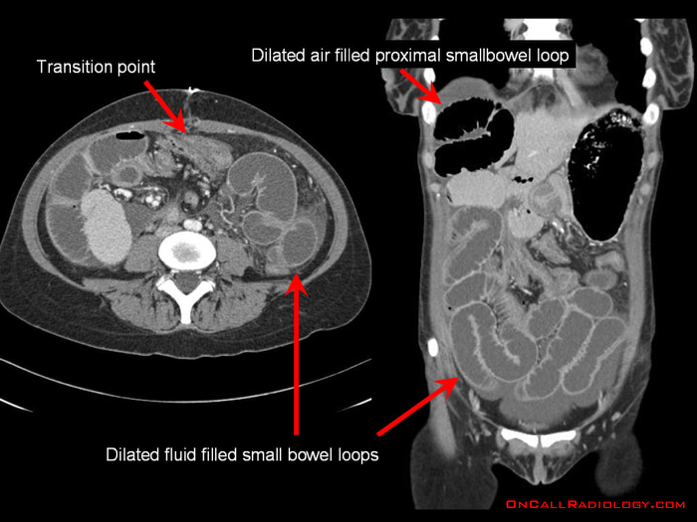

- Abdominal CT

- Much more sensitive and can also identify the specific causes

- Can also identify a transition point

- Other radiological signs on CT consistent with SBO include:

- Bowel wall thickening > 3mm

- Submucosal edema

- Mesenteric edema

- Ascites

- Target sign (intussusception)

- Whirl sign (volvulus)

- Venous cut-off sign (thrombosis)